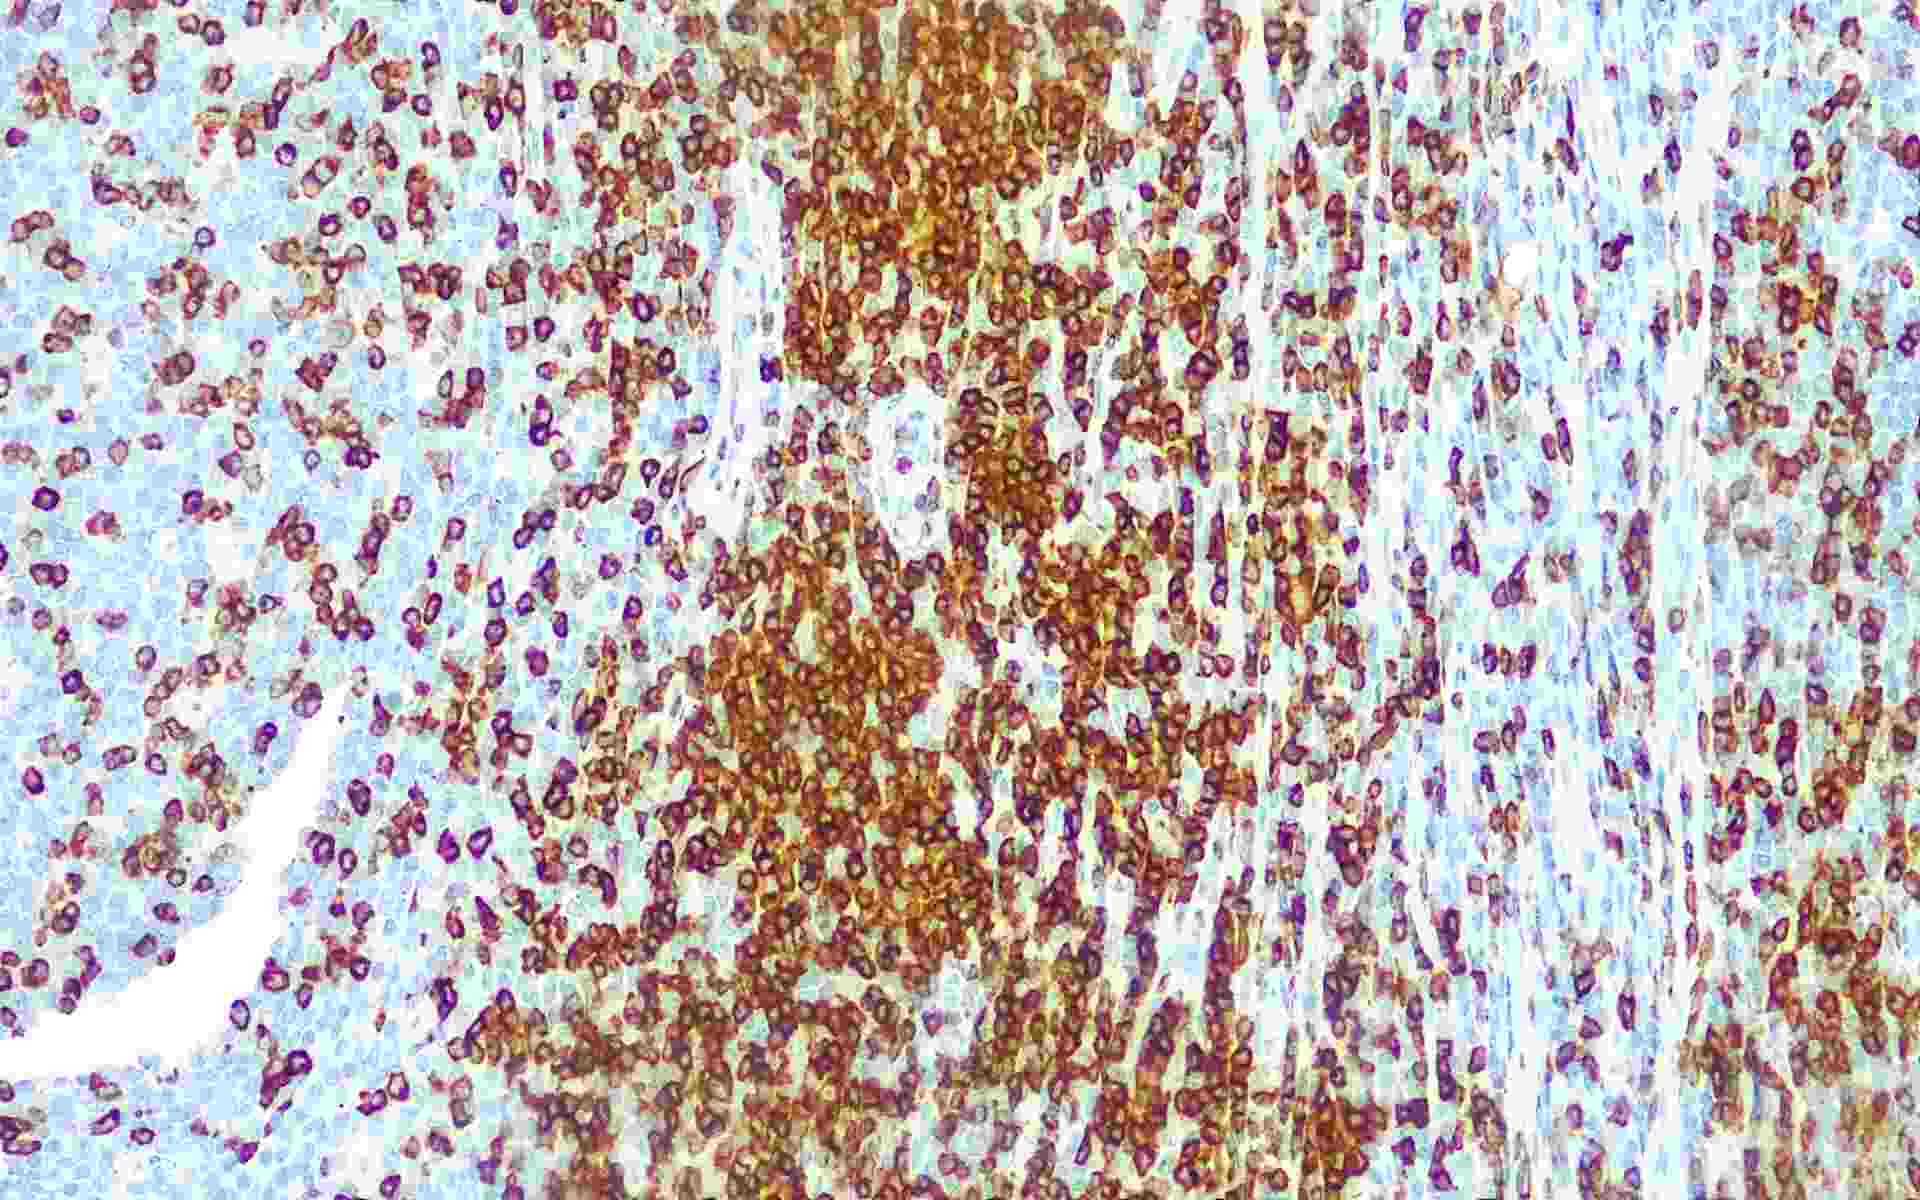

• CD7扁桃体

• 染色定位 : 细胞膜

CD7是一种分子量为40kDa的细胞膜糖蛋白,是早期T细胞和NK细胞抗原,表达于绝大多数的T细胞和自然杀伤细胞,属于免疫球蛋白超级基因家族。CD7主要用于T淋巴细胞淋巴瘤和白血病的分类。CD7在85%的外周T细胞、NK细胞、髓细胞、T细胞急性淋巴细胞白血病/淋巴瘤、急性粒细胞性白血病和慢性粒细胞白血病中表达。